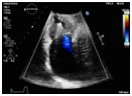

图4.术前(左)与术后(右)经食道脉冲多普勒肝静脉血流图

患者术后第二天即可自主下地活动,行动自如,原有的不适症状明显减轻,术后两天出院,出院前经胸超声多普勒检查显示三尖瓣少量反流,反流分级1+(图5)。

(图5.出院前经胸彩色多普勒超声图)